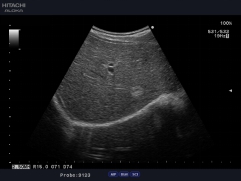

血流剖面圖

常規(guī)用多普勒方式測量血流速度只能測量某一點的速度,因此,測量血流量具有一定的局限性,日立阿洛卡推出的血流速度分布圖技術(shù)成功解決了此問題, 通過此技術(shù),醫(yī)生可以方便地得到整個血管剖面上的每一點的血流速度,從而準確計算出血管的流量。血流速度分布圖技術(shù)也可用于心排量的計算。

自動IMT測量

自動IMT檢測與手動測量相比提高了準確性,更方便,分辨率為0.01mm。系統(tǒng)可以自動描記并顯示結(jié)果和直方圖,直方圖可以更加直觀的觀察病變數(shù)據(jù),為動脈硬化的準確診斷提供了更為方便的工具。